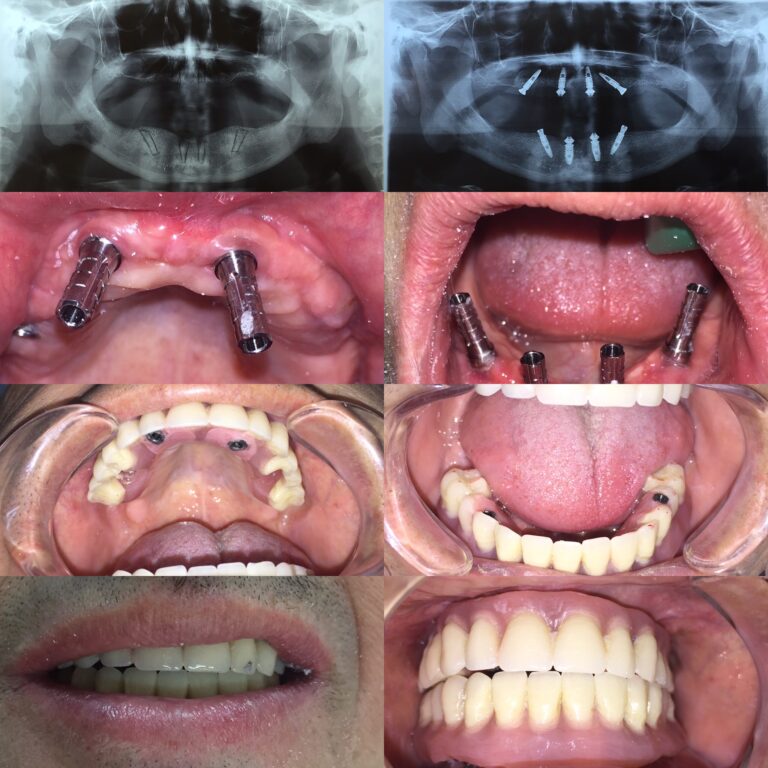

Implantes Cigomáticos y Mandibulares “all on four”

Los implantes cigomáticos son una alternativa a los implantes dentales convencionales para pacientes...